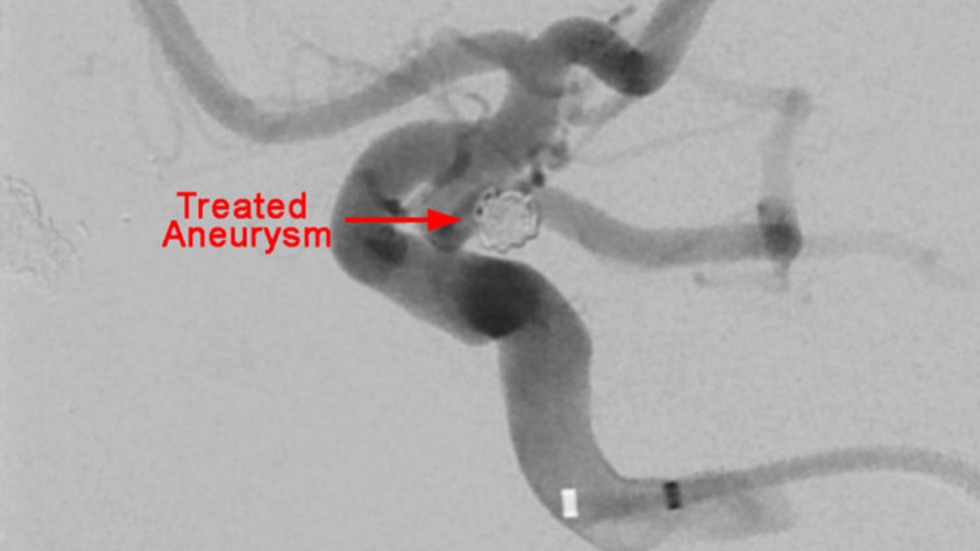

Endovascular Repair

Endovascular (from within the blood vessel) surgery, is performed through a catheter (a hollow, flexible tube) delivered from the groin or leg to the blood vessels in the brain. Thin platinum wires are pushed into the aneurysm, where they conform to the wall of the aneurysm forming a coil mass. Since blood clots form around the coils, the chances of a rupture are greatly reduced. Recovery time is typically only one to three days.

Primary Coil Embolization, Technique: Aneurysm

Primary Coil Embolization: Treats aneurysm from the inside rather than the outside. Fill aneurysm with embolic coils in order to obliterate blood flow.

Technique: Treated Aneurysm

3 of 3